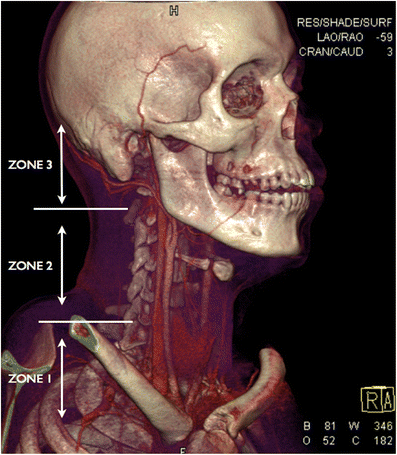

Three-dimensional volume rendering technique (3D VRT) of MDCTA performed on a young male victim of a stab wound to the neck demonstrating the anatomical trauma zones in penetrating injury of the neck. In this young patient, the cricoid cartilage has not yet calcified and therefore is not visualised on the VRT but the thyroid gland is visible (the lower border of the cricoid cartilage will be located just above the level of the isthmus of the thyroid gland)